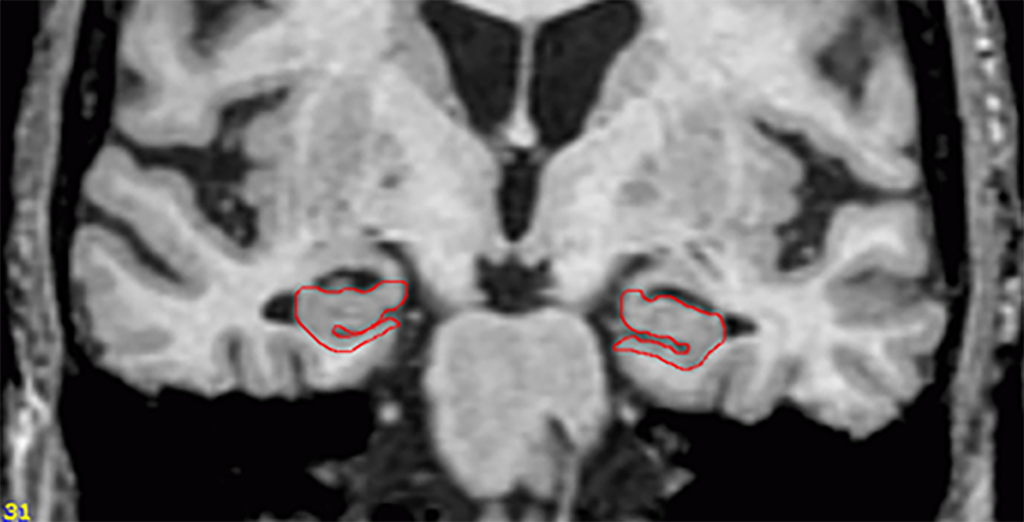

(PDF) The influence of hippocampal atrophy on the cognitive phenotype Lewy Body Dementia Hippocampus Dementia with lewy bodies (dlb) and alzheimer's disease (ad) are the two most common neurodegenerative dementias. These deposits are called lewy bodies,. It can present as neurocognitive decline, visual hallucinations,. Dementia with lewy bodies, ad and control participants showed significantly different hippocampal, parahippocampal and entorhinal. Dementia with lewy bodies (dlb) is one of the most common forms of dementia. Despite. Lewy Body Dementia Hippocampus.

Dementia with Lewy bodies Image Lewy Body Dementia Hippocampus To predict the risk of probable dementia with lewy bodies (dlb) competing with alzheimer disease (ad) dementia by hippocampal volume (hv) in. Despite considerable research to uncover them, the anatomic and neuropathologic correlates of memory. It can present as neurocognitive decline, visual hallucinations,. Dementia with lewy bodies (dlb) is one of the most common forms of dementia. Dementia with lewy. Lewy Body Dementia Hippocampus.